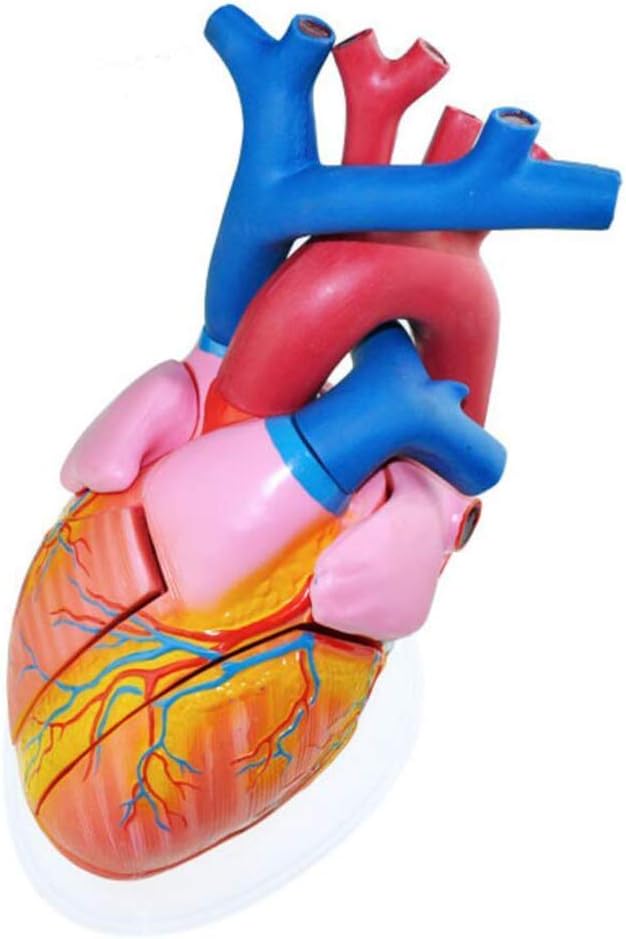

medical device

medical device